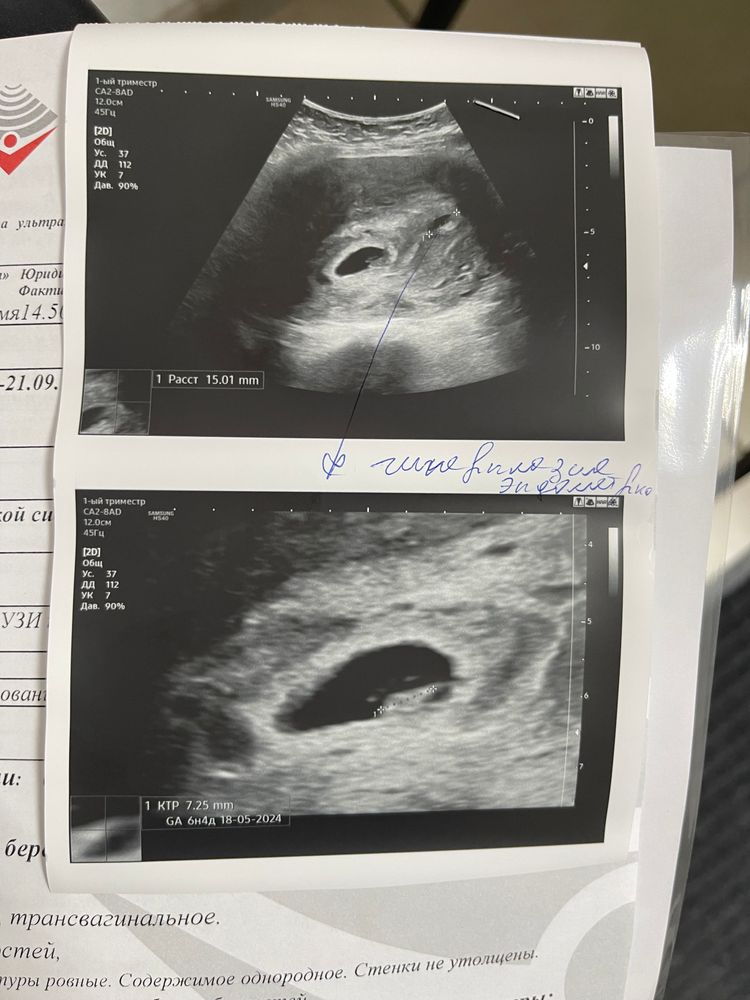

Сегодня была первый раз на узи , срок немного меньше чем по месячным , 6нед и 4 дня ,послушала сердечко 🧡 чсс 149 у/мин. В заключении гиперплазия эндометрия, кто-нибудь сталкивался с таким?